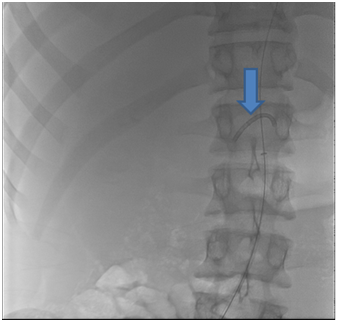

A 19 years old male patient, who was suffering from severe hypertension which was not controlled despite 5 antihypertensive drugs. Routine investigations revealed high serum creatinine 7.3mg/dl, serum K; 2.8meq/L with normal other lab results. The patient urine output was approximately 1000 ml per day. On examination, blood pressure was 240/110, bilateral midzonal and basal crepitation of chest, mild bilateral lower limb edema, and respiratory rate was 32/minute and hypoxia (So2 was 85 %) were reported. Therefore, the patient received oxygen support and hemodialysis (HD) session with ultra filtration of 4 liters on a provisional diagnosis of pulmonary edema with improvement of the patient. Renal ultrasound revealed small sized atrophic pyelonephritic left kidney and the right kidney size was 12.5*4 cm with normal sonoghraphic appearance. Renal Doppler showed absent diastole in most of waves of the right renal vessels, resistive index (RI) of right main renal artery was 0.82 with peak systolic velocity (PSV) 22 cm/s and RI of right intrarenal artery was 0.87 with PSV 12.7cm/s. Right renal artery stenosis was diagnosed and confirmed by computed tomography angiogram (CTA) which detected single right renal artery with narrowing of its caliber at the proximal part (16 mm) (Figure 1). Renogram had shown severe parenchymal tracer (MAG3) retention in the affected right kidney mostly due to renal artery stenosis and non-functioning left one. Thus, right renal angioplasty with stenting was decided. But, the procedure complicated with broken guide catheter tip (about 3 cm lengths) and the distal part was impacted in the renal artery and the proximal part in the aorta (Figure 2). Consequently, immediate abdominal exploration was done for removal of the broken part. The surgery passed smoothly and the patient referred to ICU with stable hemodynamics. The patient maintained on HD and hypertensive drugs for 3 weeks then the patient underwent a successful right renal angioplasty with two stents fixation (Figure 3).The blood pressure and serum creatinine started to improve, HD was stopped and the patient was discharged after 2 weeks with serum creatinine 0.9mg/dl, four antihypertensive drugs, warfarin and aspirin with cessation of warfarin six months later. Currently, the patient has maintained on 2 antihypertensive drugs, aspirin with stable kidney function and controlled blood pressure.

Figure 2 The broken guide catheter tip (about 3 cm length) with the distal end in the right renal artery and the proximal end in the aorta (the arrow).